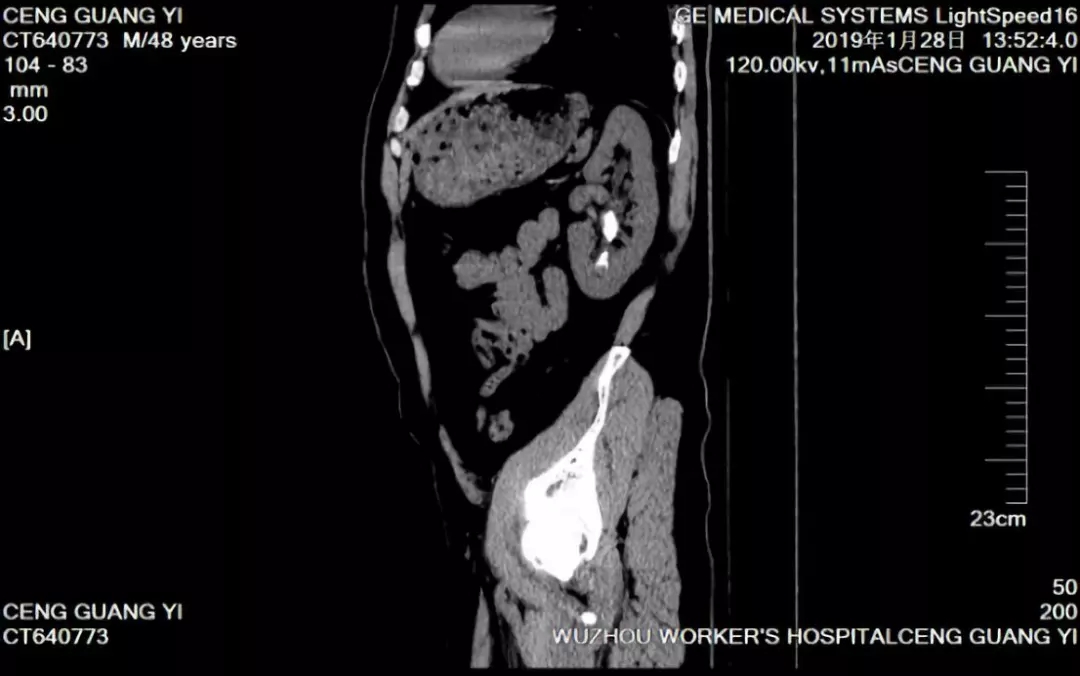

患者曾先生,48岁,因“反复左侧腰痛伴发热血尿半月余”,曾经四处求医,尝试过药物排石及体外震波碎石等治疗方法,但收效甚微。经了解,曾先生前来梧州市工人医院泌尿外科就诊。入院检查后,医生诊断为左肾铸型结石伴感染。

(图为曾先生术前检查CT片)